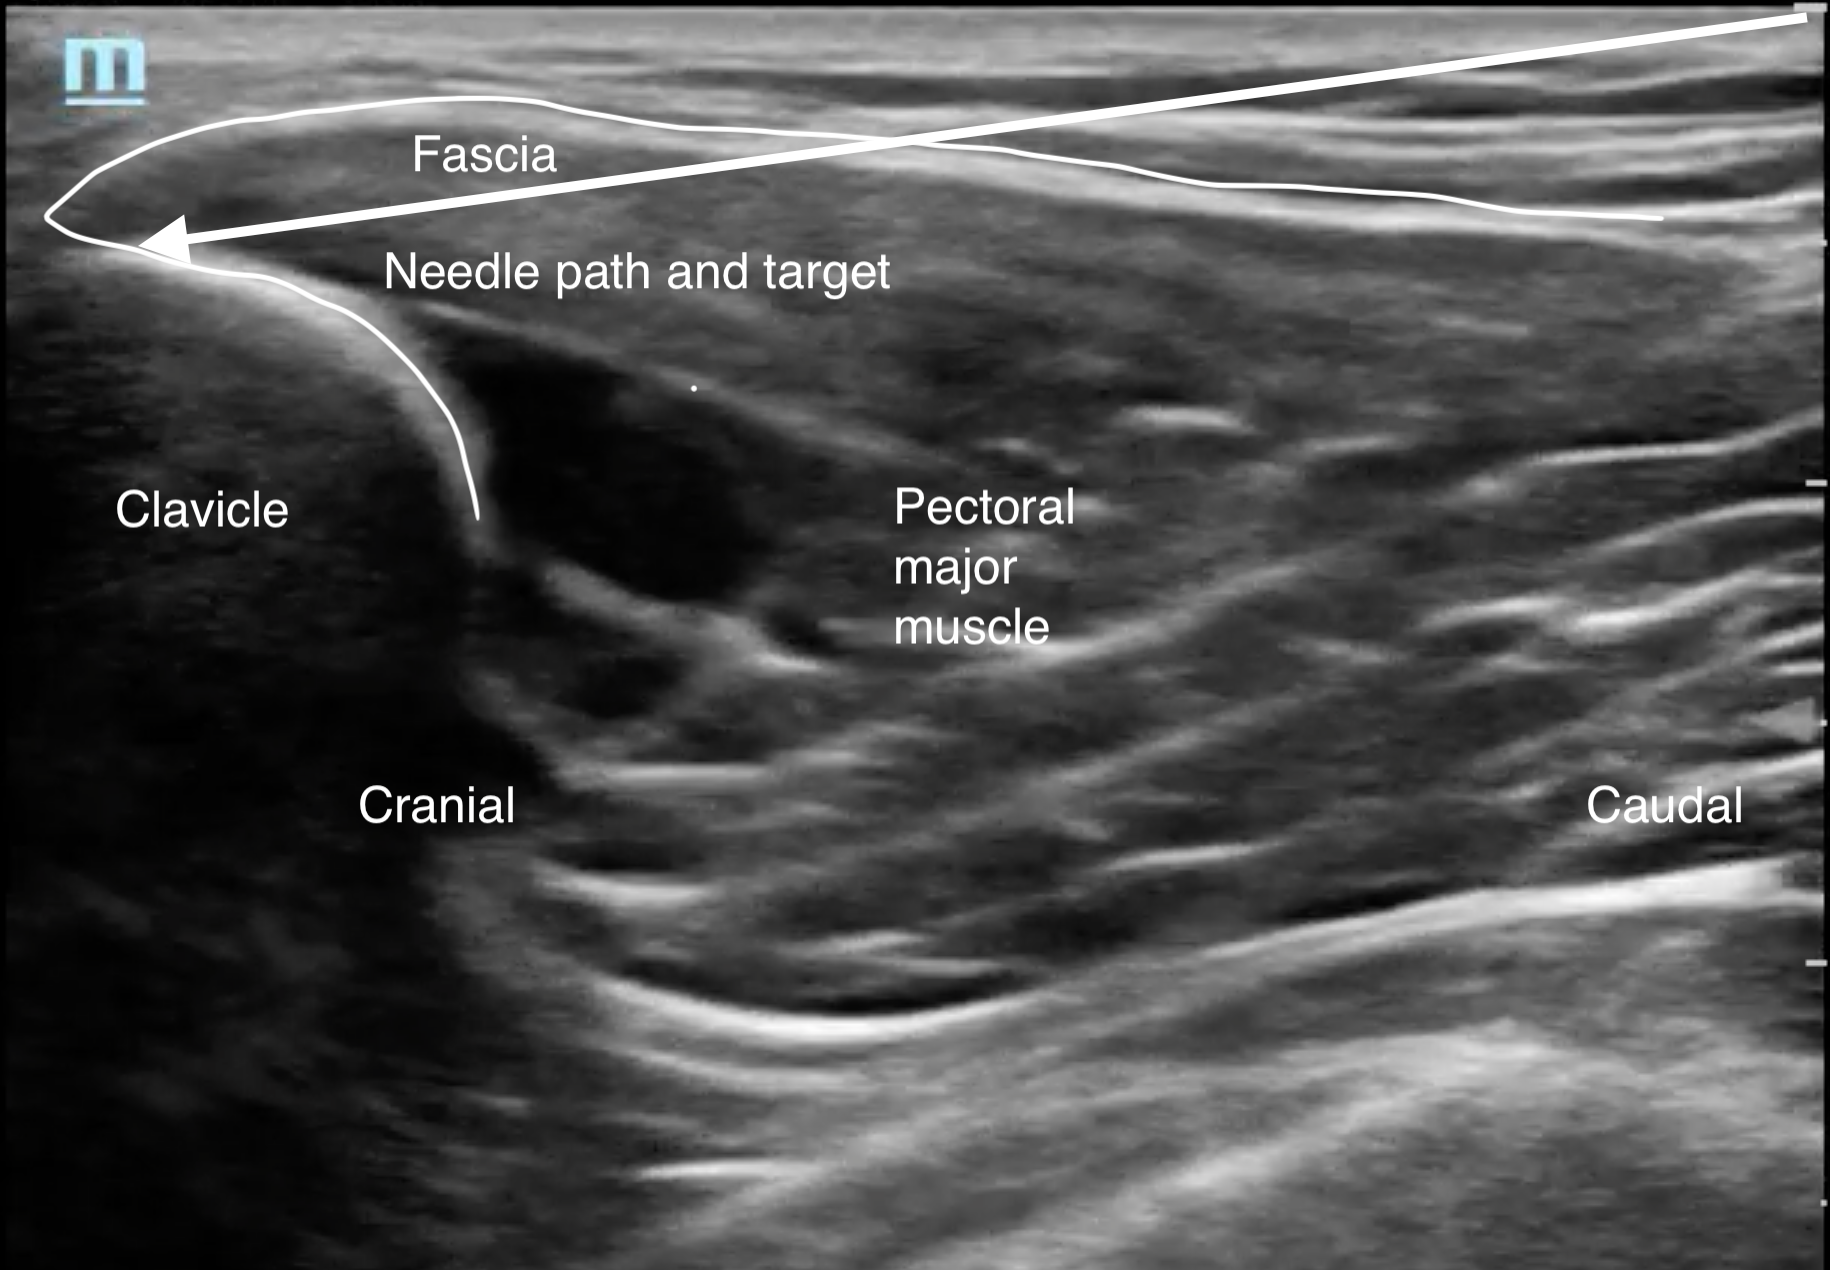

Clavipectoral fascial plane block

劑量雙側各10-15 ml ,Bupivacaine 0.5% or Ropivacaine 0.5%

參考鎖骨 / 胸大肌 / 筋膜 (圖片3、影片3)

圖片3Clavipectoral fascial plane block (CPFB)示意圖

影片3Clavipectoral fascial plane 超音波影像

定位縱向放在鎖骨骨折近遠端完整骨頭處,由胸部往頭側水平入針,經過胸大肌,針尖停靠在鎖骨正上方筋膜處